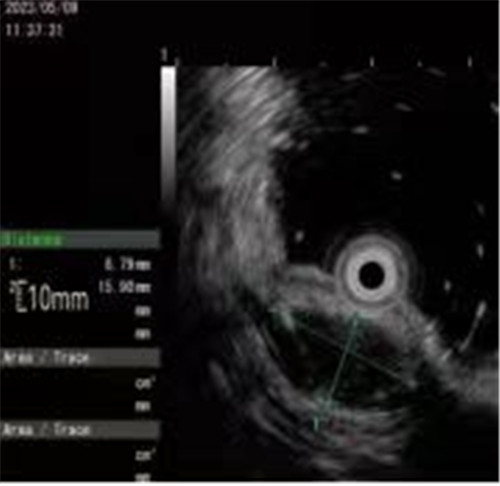

近期病例之一,圖片依次為:胃鏡、超聲胃鏡、ESE術(shù)中、術(shù)后、切下病變。

內(nèi)鏡超聲小探頭可用于探查消化道管壁腫物。消化道管壁分為4層,從內(nèi)到外依次為粘膜層、粘膜下層、肌層、漿膜層,不同分層內(nèi)的病變性質(zhì)各異。

內(nèi)鏡超聲小探頭可以判斷病變的起源、回聲性質(zhì)、生長方式、大小等,從而協(xié)助醫(yī)生制定相應(yīng)的診療方案,也被稱作是普通內(nèi)鏡醫(yī)生的“透視眼”。